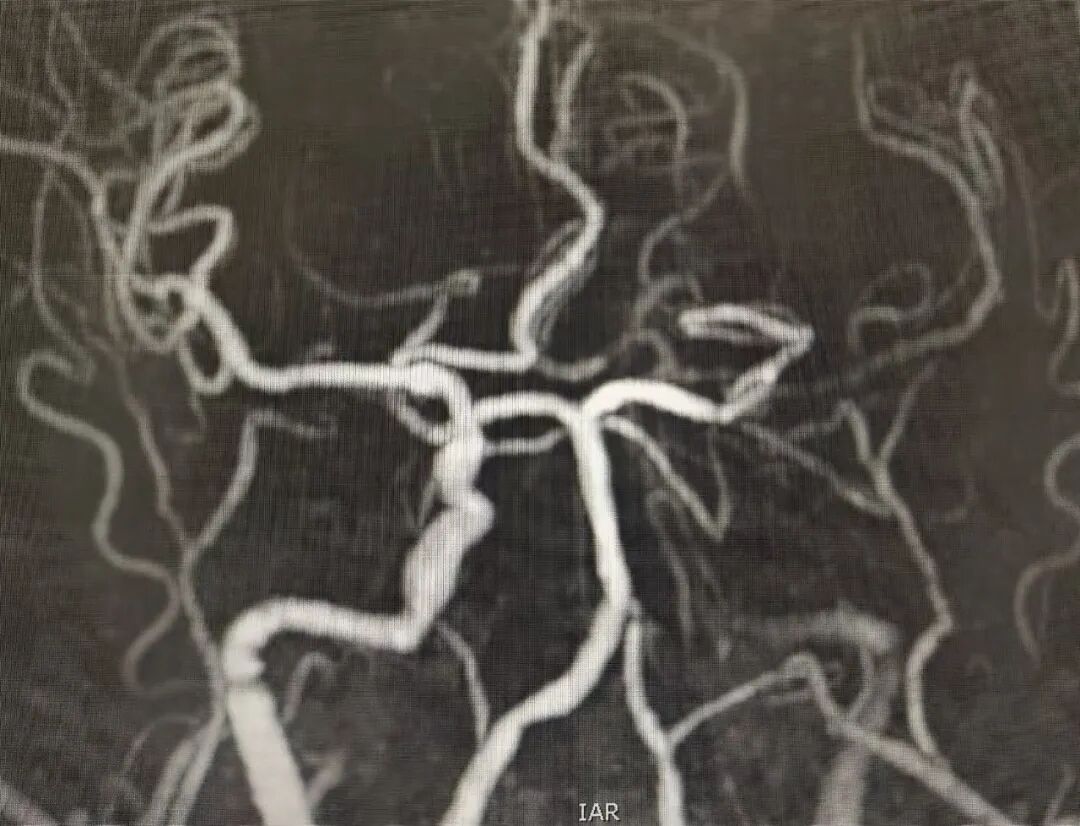

明确患者符合急诊溶栓指征后,该院神经外科团队果断实施急诊溶栓治疗,为血管再通争取宝贵时间。溶栓治疗后,团队根据患者病情,进一步制定“急诊脑血管造影 + 动脉取栓”的精准治疗方案。

手术室和麻醉科早已提前做好充分准备。患者转运至手术室后,麻醉团队迅速完成麻醉诱导。神经外科医生凭借丰富的临床经验与精湛技术,在造影设备的精准引导下,小心翼翼地将取栓器械送至闭塞的颈内动脉处,成功取出栓子。当造影图像显示闭塞血管重新通畅、脑部血流恢复正常时,在场所有医护人员悬着的心终于稍稍放下。